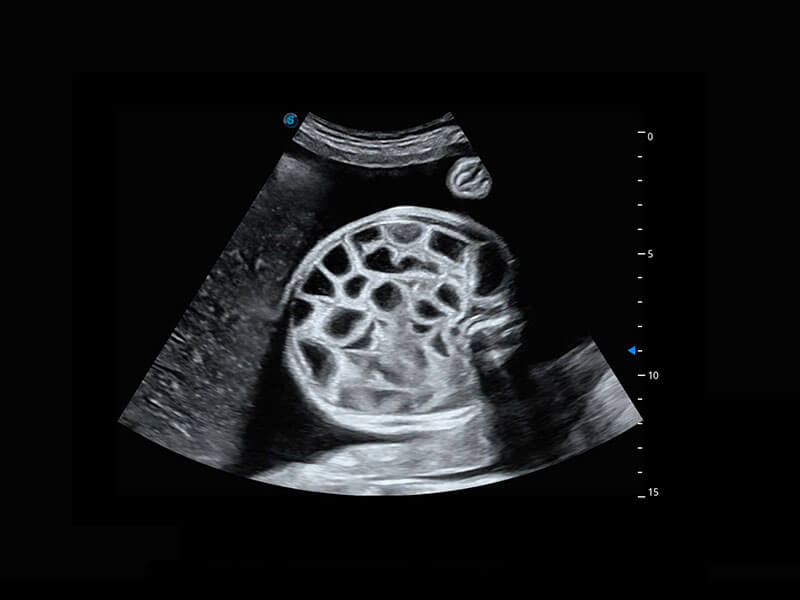

P60搭载一系列胎儿心脏成像技术,实现精细的胎儿心脏评估。

四腔切面

四腔心血流

胎心容积成像